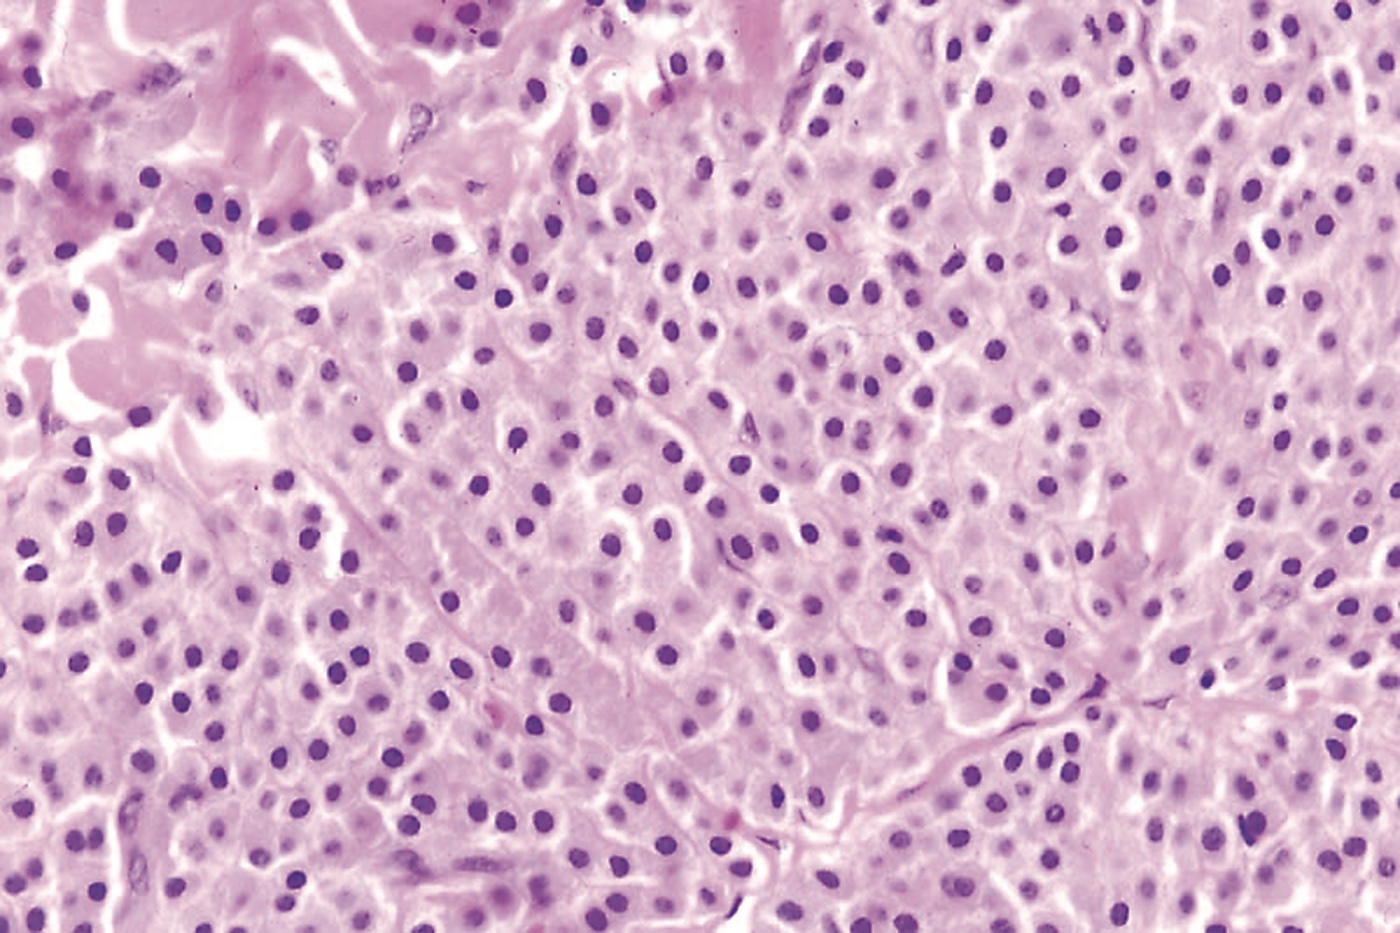

Solitary mastocytoma is usually a clinical diagnosis.4 Episodes of swelling and bulla formation are helpful diagnostic clues.3 The Darier sign is virtually pathognomonic for mastocytoses. Because the disseminated form may begin with a single lesion and dissemination usually occurs within 3 months of onset, the diagnosis of a solitary mastocytoma should not be made unless the single lesion has persisted for more than 3 months.3 Skin biopsy is usually only required in atypical cases.4 Histologically, mastocytomas may show a mast cell infiltrate in the papillary dermis, with variable extension through the reticular dermis and into the subcutaneous fat (Figure 3).3 When the diagnosis is in doubt, consider a referral to a dermatologist.

Figure 3.